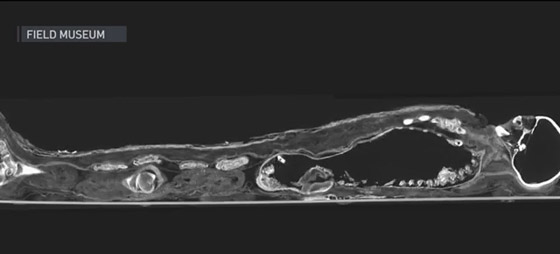

عاشت السيدة "شينيت-آه" منذ حوالي 3 آلاف عام خلال عهد الأسرة الثانية والعشرين في مصر. وساعدت المسوحات الجديدة العلماء في تقدير أنّ المرأة ذات المكانة العالية توفيت بين أواخر الثلاثينيات وأوائل الأربعينيات من عمرها. وقالت دريك إنّه تم وضع حشوة في قصبتها الهوائية لضمان عدم انهيار رقبتها، ووُضِعت عيون اصطناعية في تجاويف العيون لضمان تواجدهما في الحياة الآخرة.

وتم لف "شينيت-آه" بطبقات باهظة الثمن من الكتان قبل وضعها في تابوت مزخرف يشبه الورق المعجن. ولكن تمحور اللغز الأكبر بشأنها حول كيفية وضعها بالصندوق في المقام الأول. لم تكن هناك شقوق مرئية في التابوت، وتواجدت فقط فتحة صغيرة عند القدمين، ولكنها لم تكن واسعة بما يكفي لإدخال الجثة إلى الصندوق.

وأفاد براون أنّ عمليات المسح الجديدة كشفت ولأول مرة عن الجزء السفلي من الكرتوناج (خليط من الكتان، والصمغ، والجص وفقًا لموقع وزارة الآثار المصرية)، حيث أظهرت أنّ الصندوق كان مغلقًا بإحكام من الخلف قبل تغطيته بالجص لخلق مظهر سلس. وقال الفريق إنّ المحنطين وضعوا المومياء في وضع قائم، وقاموا بتليين الكرتوناج لجعله مرنًا حتى يتمكنوا من تشكيله بشكل محكم حول الجسم.

ومن ثم تم قطع شق في الجزء الخلفي من الكرتوناج لوضع الجسم بالداخل، وتم إغلاقه بعد ذلك. ألقى الفريق أيضًا نظرة فاحصة على "هاروا" (Harwa)، وهو شخص محنط عاش منذ حوالي 3 آلاف عام، وكان حارسًا لصومعة. ويُظهر تحليل لعمليات المسح أنّه كان في أوائل إلى منتصف الأربعينيات من عمره عندما توفي، وكان قد تمتع بمكانة اجتماعية عالية، وعاش حياة مريحة. وأوضحت دريك: "بدأنا بالنظر إلى هذين الفردين في المقام الأول فقط للحصول على فكرة أفضل عن العمر، والنوع، وأي أمراض أو أشياء واضحة قد نراها".